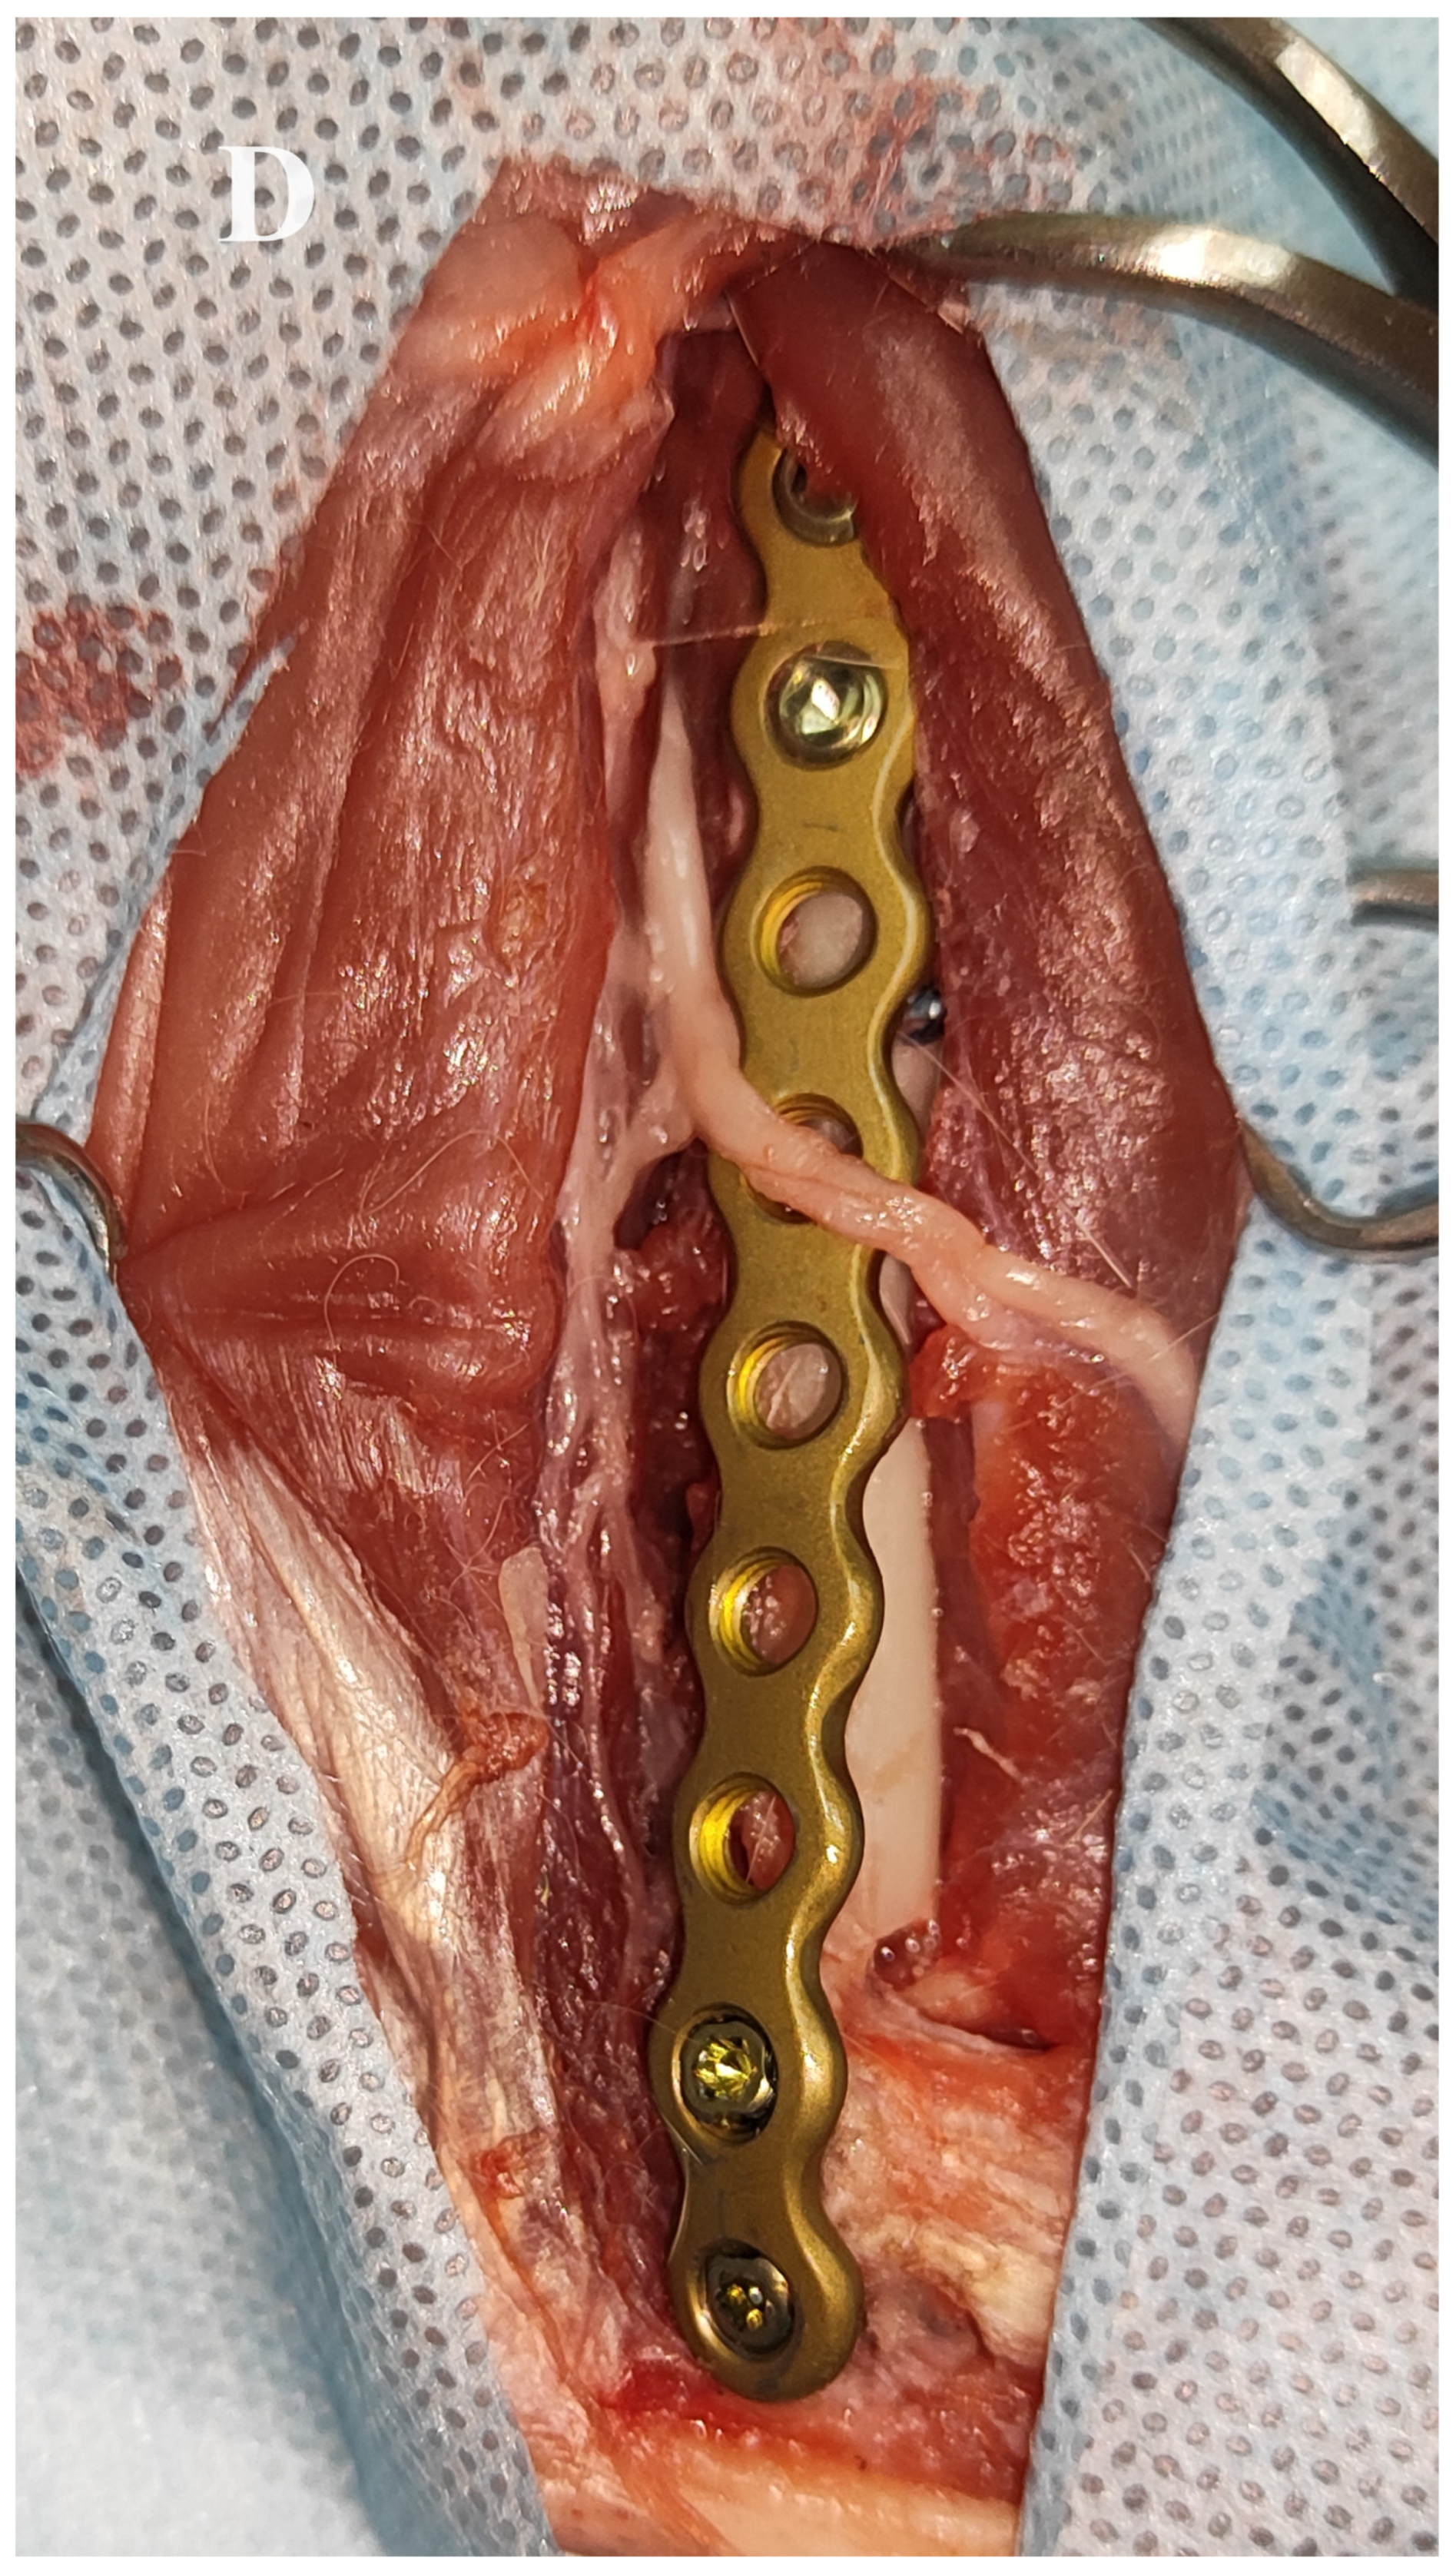

The fractures were exposed by combined medial and lateral approaches to the humerus. Care was taken to avoid injury to the neurovascular structures. In all procedures, a medial approach to the humerus was first performed to treat the medial condylar fracture in order to transform the bicondylar fracture into a lateral monocondylar fracture. To ensure good implant positioning and to avoid impingement of the neurovascular structures by the plate, cranial retraction of the brachial artery, vein and median nerve was performed after freeing these structures from the supracondylar foramen by removing its medial border with a rongeur as described by Maritato et al. [19]. In addition, the origin of the medial head of the triceps brachii muscle was transected and retracted caudally. The medial surface of the humeral condyle was partially exposed after combined blunt and sharp dissection between the pronator teres muscle and the antebrachial flexor muscles. Then, a custom-made anatomically pre-contoured interlocking plate was used to reduce and stabilise the medial aspect of the humeral condyle to the humeral diaphysis. The medial part of the humeral condyle was initially stabilised with a 1 mm Kirschner wire inserted through the medial epicondyle and a 2 mm locking screw (Iwet, Grabówka, Poland). The shaft of the plate was first stabilised with 1 mm Kirschner wires and then with 2.4 mm locking screws (Iwet, Grabówka, Poland) (Figure 3 and Figure 4). A lateral approach to the distal humerus allowed reduction and stabilisation of the intracondylar aspect of the fracture with pointed reduction forceps. A 2.7 mm preloaded positional locking screw was then inserted from the medial to the lateral side between pronator teres muscle and antebrachial flexors and a 2.4/2.7 interlocking bone plate (Medgal, Księżyno, Poland) was used to stabilise the lateral part of the condyle to the humeral diaphysis (Figure 5). In cases with additional humeral shaft fractures, cerclage wires were used to support the bone plates.

Figure 3.

Reduction and stabilisation of the Y-T fracture of the right humerus on the 3D printed bone model. (A–C) After conversion of the bicondylar fracture to a monocondylar lateral fracture using the printed plate, the lateral part of the fracture was stabilised with a 2.4/2.7 locking plate.

Figure 4.

Medial approach to the right humerus and insertion of the 3D printed plate in an adult female domestic cat. (A,B) Exposure of the medial surface of the right humerus. Release of the brachial artery, brachial vein and median nerve from the supracondylar foramen after removal of its medial border (asterisk). Exposure of the medial part of the humeral condyle (grid) after dissection between the pronator teres muscle and the antebrachial flexor muscles. Conversion of the bicondylar fracture to a monocondylar fracture using the printed plate. (C,D) Final stabilisation of the medial and lateral part of the Y-T fracture.